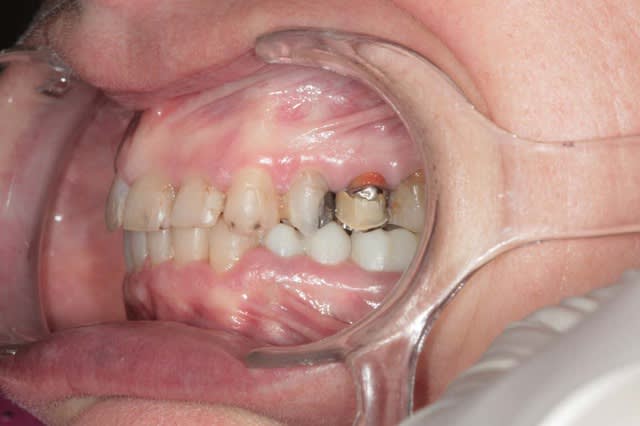

Récemment Céramik râlé, parce qu'il n'y avait pas de nouveau cas (esthétique je crois) à se mettre sous la dent. Je me jettes à l'eau avec ce dernier cas posé ce vendredi (y'a pas plus frais), une larme à l'oeil parce qu'il s'agit aussi du dernier gros cas dans mon cabinet que je quitte cette semaine pour rejoindre ma belle et nos p'tits bouts loin la bas dans le sud.

La patiente a un sourire très médiocre avec migration de plus en plus marqué du bloc incisivocanin sup. Comment l'aidez vous?

Cas de ré-hab globale comme j'aime bien

Ouverture de DV, et correction de la classe 2 par repositionnement mandibilaire

Chirurgie paro ant sup

Tous est à refaire dans cette bouche, amalgames horibles, couronne brisée, etc

Céramiques haut et bas, au complet